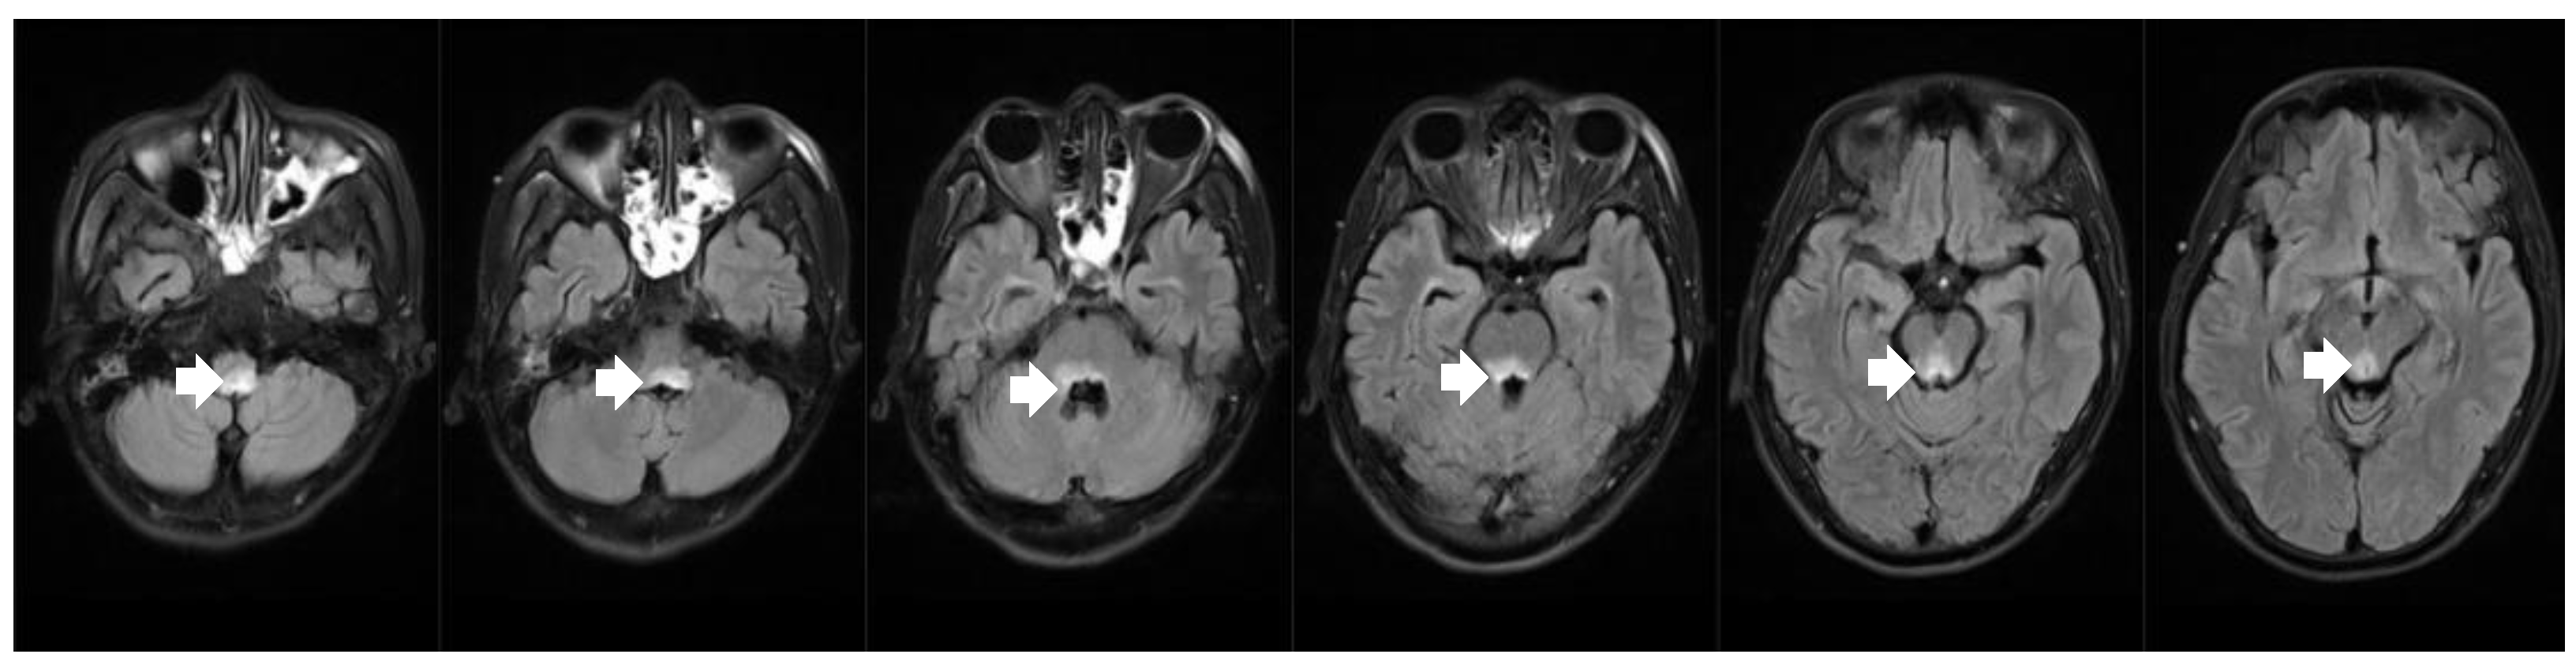

3.1. Case 1

3.2. Case 2

| Patient No. | Age | Sex | Arrhythmia | Neurological Symptoms | MRI Findings | History of Heart Diseases | Treatment for NMOSD |

|---|---|---|---|---|---|---|---|

| 1 [4] | 78 | M | Cardiac arrest | Syncope, orthostatic hypotension, APS, lower limb weakness | Medulla oblongata and cervical cord | No | IVMP, IVIG |

| 2 [5] | 21 | F | Cardiac arrest | APS | Medulla oblongata | No | IVMP, RTX |

| 3 [6] | 77 | M | Sinus arrest | APS | Medulla oblongata | CHD | Oral prednisolone |

| 4 [7] | 61 | F | Sinus arrest | Syncope, APS | Medulla oblongata | No | IVMP |

| 5 [8] | 42 | M | Sinus arrest | Syncope, APS, left optic neuritis | Medulla oblongata and left optic nerve | No | IVMP |

| 6 [9] | 77 | F | Sinus arrest | Syncope, APS, limb weakness | Medulla oblongata and cervical cord | No | IVMP, PE |

| 7 [10] | 16 | M | Sinus bradycardia | APS | Medulla oblongata | No | IVMP |

| 8 [11] | 22 | F | Sinus arrest | APS, syncope, diplopia and hypesthesia | Medulla oblongata and cervical cord | No | IVMP |

| 9 | 45 | M | Sinus arrest | Syncope, APS | Medulla oblongata | No | IVMP, IVIG |

| 10 | 26 | M | Cardiac arrest | APS, limbs weakness, dysphagia, diplopia | Medulla oblongata, pons and mesencephalon | No | IVMP, PE, IVIG |